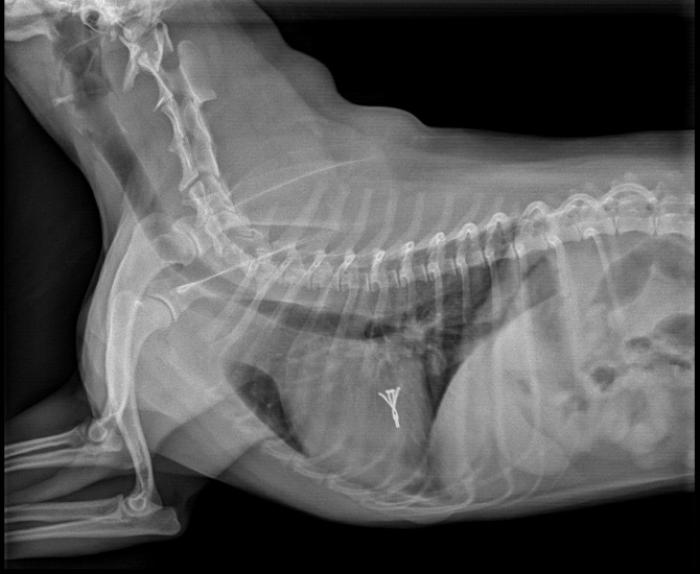

Se concluyó la intervención con cierre de la apertura ventricular, colocación de tubo de drenaje pleural y cierre por planos de la intervención quirúrgica. El paciente fue hospitalizado, donde la radiografía post quirúrgica inmediata mostró correcta posición del dispositivo. A las 8 horas post-intervención el paciente se mostró activo, con interés por comer, y sin presencia de alteraciones en presión arterial, frecuencia cardíaca, frecuencia respiratoria y temperatura. Se observó en el electrocardiograma de superficie la presencia de ectopias ventriculares y ritmo idioventricular acelerado de forma paroxística y autolimitarte, que se resolvió espontáneamente sin empleo de tratamiento antiarrítmico.

A la semana de intervención el paciente se presentó en consulta para revisión de ecocardiografía y los parámetros obtenidos mostraron una mejoría de la clasificación ACVIM pasando a fase B2, con un índice MINE de 5 puntos, mejorando a un grado leve (ver Tabla 1). En ese momento el tutor comentó que presentaba un estado general correcto, había presentado vómitos aislados y tenía un ligero seroma en el área de intervención. Se realizó hemograma el cual mostró una leve leucocitosis y el análisis bioquímico descartó aumento en los valores de urea y creatinina. El estudio radiográfico en ese momento evidenció reducción significativa del atrio izquierdo, con ausencia de signos compatibles con congestión pulmonar (Figura 3). En consecuencia, se optó por modificación del tratamiento ambulatorio y reducción de la dosis de Furosemida (1mg/kg BID) y continuar con misma dosis de Pimobendán (0.25mg/kg BID) de manera crónica hasta la siguiente visita al cabo de un mes.